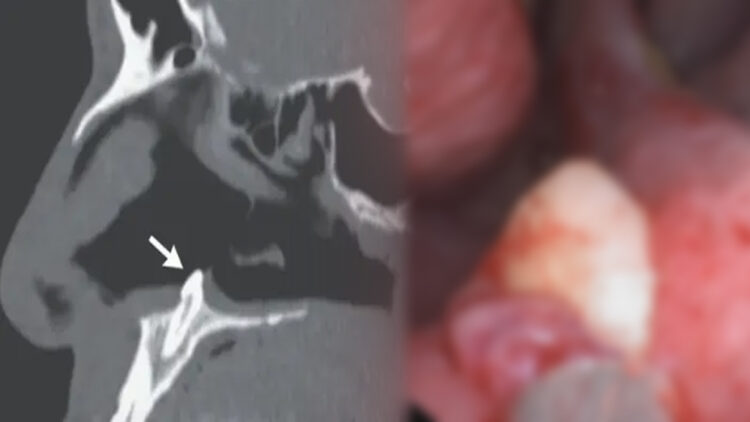

അങ്ങനെ നിരാശനായി ജീവിതം മുന്നോട്ട് കൊണ്ട് പോകുന്നതിനിടയിൽ അവസാന ശ്രമം എന്ന നിലയ്ക്ക് അദ്ദേഹം ന്യൂയോർക്കിലെ മൗണ്ട് സിനോയ് എന്ന് ആശുപത്രിയെ സമീപിച്ചു. അവിടുത്തെ വിദഗ്ധ പരിശോധനയിൽ അദ്ദേത്തിന്റെ നാസാരന്ധ്രങ്ങയളെ വേർതിരിക്കുന്ന ഭാഗത്തിൽ ഒരു വ്യതിയാനം കണ്ടു പിടിച്ചു. മുക്കിന്റെ പാലത്തിന് പിൻവശത്തായി രണ്ട് സെന്റീമീറ്റർ വലുപ്പത്തിൽ ഒരു ദ്വാരവും അതിന് സമീപത്തായി 14 മില്ലീമീറ്ററോളം നീളമുള്ള പല്ലും കണ്ടെത്തി. ലോകത്ത് ആകെ 0.1-1 ശതമാനം വരെ ആളുകൾക്ക് സംഭവിക്കാവുന്ന ഈ അപൂർവ്വ അവസ്ഥയാണ് യുവാവിനും നേരിടേണ്ടി വന്നത്.

മൂക്കിൽ പല്ല് മുളയ്ക്കുക എന്ന് വളരെ ലളിതമായി പറയാം. രോഗകാരണം കണ്ടു പിടിച്ചതോടെ ശസ്ത്രക്രിയയിലൂടെ യുവാവിന്റെ മൂക്കിലെ പല്ല് നീക്കം ചെയ്തു. മൂക്കിലെ പല്ല് നീക്കം ചെയ്തതോടെ യുവാവ് വർഷങ്ങളായി അനുഭവിച്ചു കൊണ്ടിരിക്കുന്ന ശ്വാസ തടസ്സത്തിനും പരിഹാരമായി. ആദ്യമായിട്ടല്ല മൂക്കിലെ പല്ല് ഇങ്ങനെ വലിയ പണികൾ കൊടുക്കുന്നത്. 2019 ൽ ഡെൻമാർക്കിലെ ഒരു അൻപതുകാര് മൂക്കിലെ പല്ല് കാരണം മണക്കാനുള്ള ശേഷി വരെ നഷ്ടപ്പെട്ടിരുന്നു.